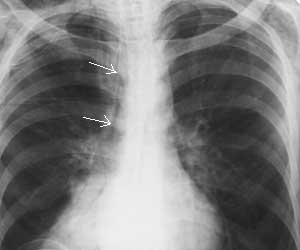

Рис. 2. Пневмомедиастинум как следствие перфорации пищевода. Полоска газа в средостении справа (стрелки).